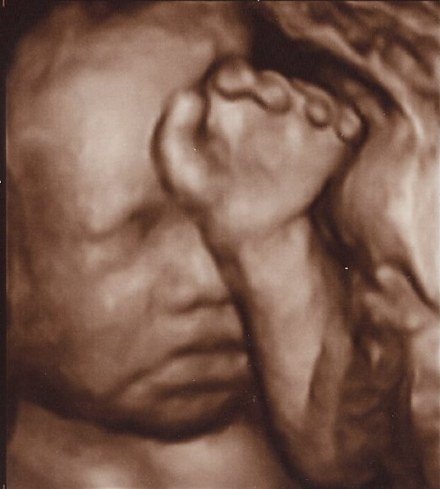

Vi glæder os sådan til at møde hende. Hende med fars næse og mund, hende som de siger har masser af hår på hovedet. Vores lækre lille halvkoreanske skønhed! Vores prinsesse, solskin og lille mirakel

Fra streger, til første mave, til NF til 3D til stor mave!